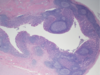

Appendix

Appendix